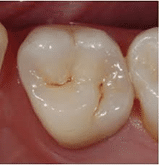

La parte del dente che mastica è formata da punte ( cuspidi ) e solchi. Quando si mastica il cibo schiacciato dai denti rimane intrappolato nei solchi, soprattutto cibi come cereali, crackers, biscotti, cioccolata, tutti alimenti, tra l’altro molto consumati dai bambini.

Rimuovere questi alimenti dal dente con lo spazzolino non è sempre facile per tre motivi, il primo è che sono residui molto consistenti e le setole fanno fatica a rimuoverli, il secondo è che i solchi molte volte sono stretti e le setole proprio non entrano in profondità a sufficienza per rimuovere il cibo in profondità, il terzo è dovuto al fatto che i bambini hanno difficoltà tecniche ad eseguire un corretto lavaggio dei denti. Quello che succede è che la parte del dente che mastica si caria proprio in età infantile.

La sigillatura consiste nel far penetrare in materiali liquido come l’acqua nei solchi ben preparati e puliti, con una lampada speciale si fa indurire il materiale che rimane intrappolato nel solco del dente. A questo punto il solco è già “pieno” del mio materiale e non si può infilare il cibo.

Il dente sigillato quindi è protetto dalla carie nella parte che mastica e che è più soggetta a cariarsi.